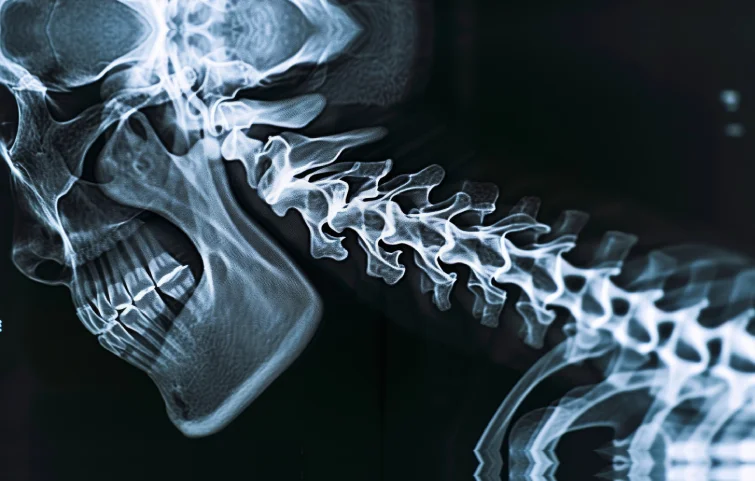

A spinal fracture refers to a break in the vertebrae, the bones that make up the spine. These fractures can result from trauma, such as an accident or fall, or from conditions that weaken the bones, such as osteoporosis. The treatment and prognosis depend on the fracture's location, type, and severity.

X-rays are the initial imaging modality used to identify fractures in the vertebral column. However, subtle or complex fractures, especially those involving the posterior elements of the spine or spinal cord, often require further evaluation using CT (Computed Tomography) scans, which provide a more detailed visualization of bony structures.